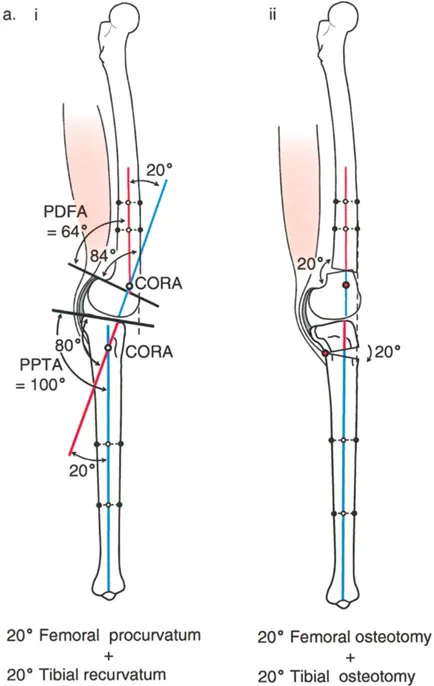

تصحيح الركبة الارتدادية (Recurvatum Deformity - Hyperextension)

الركبة الارتدادية هي فرط البسط في الركبة. غالبًا ما تكون غير مصحوبة بأعراض في الأشخاص ذوي العضلات السليمة، ولكنها قد تسبب مشاكل في حالات ضعف العضلات أو التشوهات العظمية.

- التشخيص: يجب تحديد ما إذا كانت الارتدادية عظمية (تقوس خلفي في الفخذ أو الساق) أو ناتجة عن رخاوة في الأنسجة الرخوة أو ضعف عضلي.

- قطع العظم الانثنائي (Flexion Osteotomy):

- إذا كان التشوه عظميًا (تقوس خلفي)، يتم إجراء قطع عظم انثنائي في عظم الفخذ أو الساق لتصحيح الارتدادية.

- الأستاذ الدكتور محمد هطيف يشدد على أهمية عدم استخدام قطع عظم الفخذ الانثنائي لتصحيح ارتدادية الساق، والعكس صحيح، لتجنب الانزلاق الخلفي أو الأمامي للركبة.

- اعتبارات خاصة: في المرضى الذين يعانون من ضعف عضلي (مثل شلل الأطفال)، قد يحتاج التصحيح إلى فرط تصحيح بسيط (overcorrection) إلى وضعية انثناء لضمان ثبات الركبة ومنع فرط البسط غير المتحكم فيه.